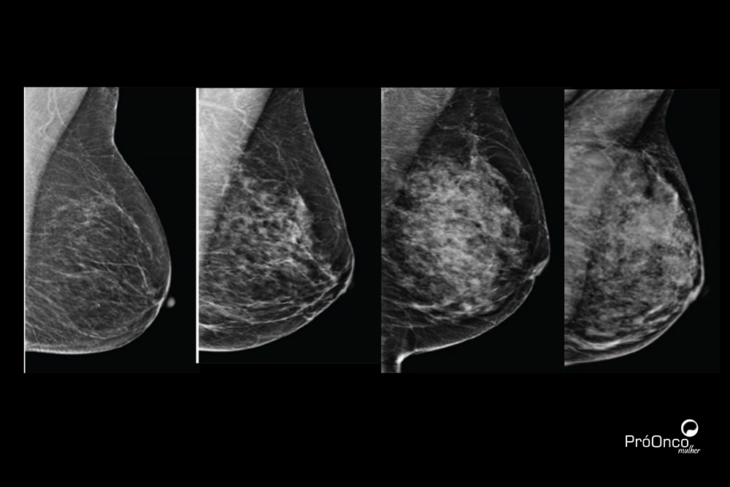

Alguns nódulos podem ser identificados pela mamografia apesar de não serem palpáveis. Nesses casos, o especialista tem necessidade do auxílio de imagens e, em outros, de um guia para chegar até a lesão no momento da cirurgia. A cirurgia de lesão não palpável é guiada através de um marcador para que o médico consiga identificar o local sem afetar a saúde da mama no momento da cirurgia.